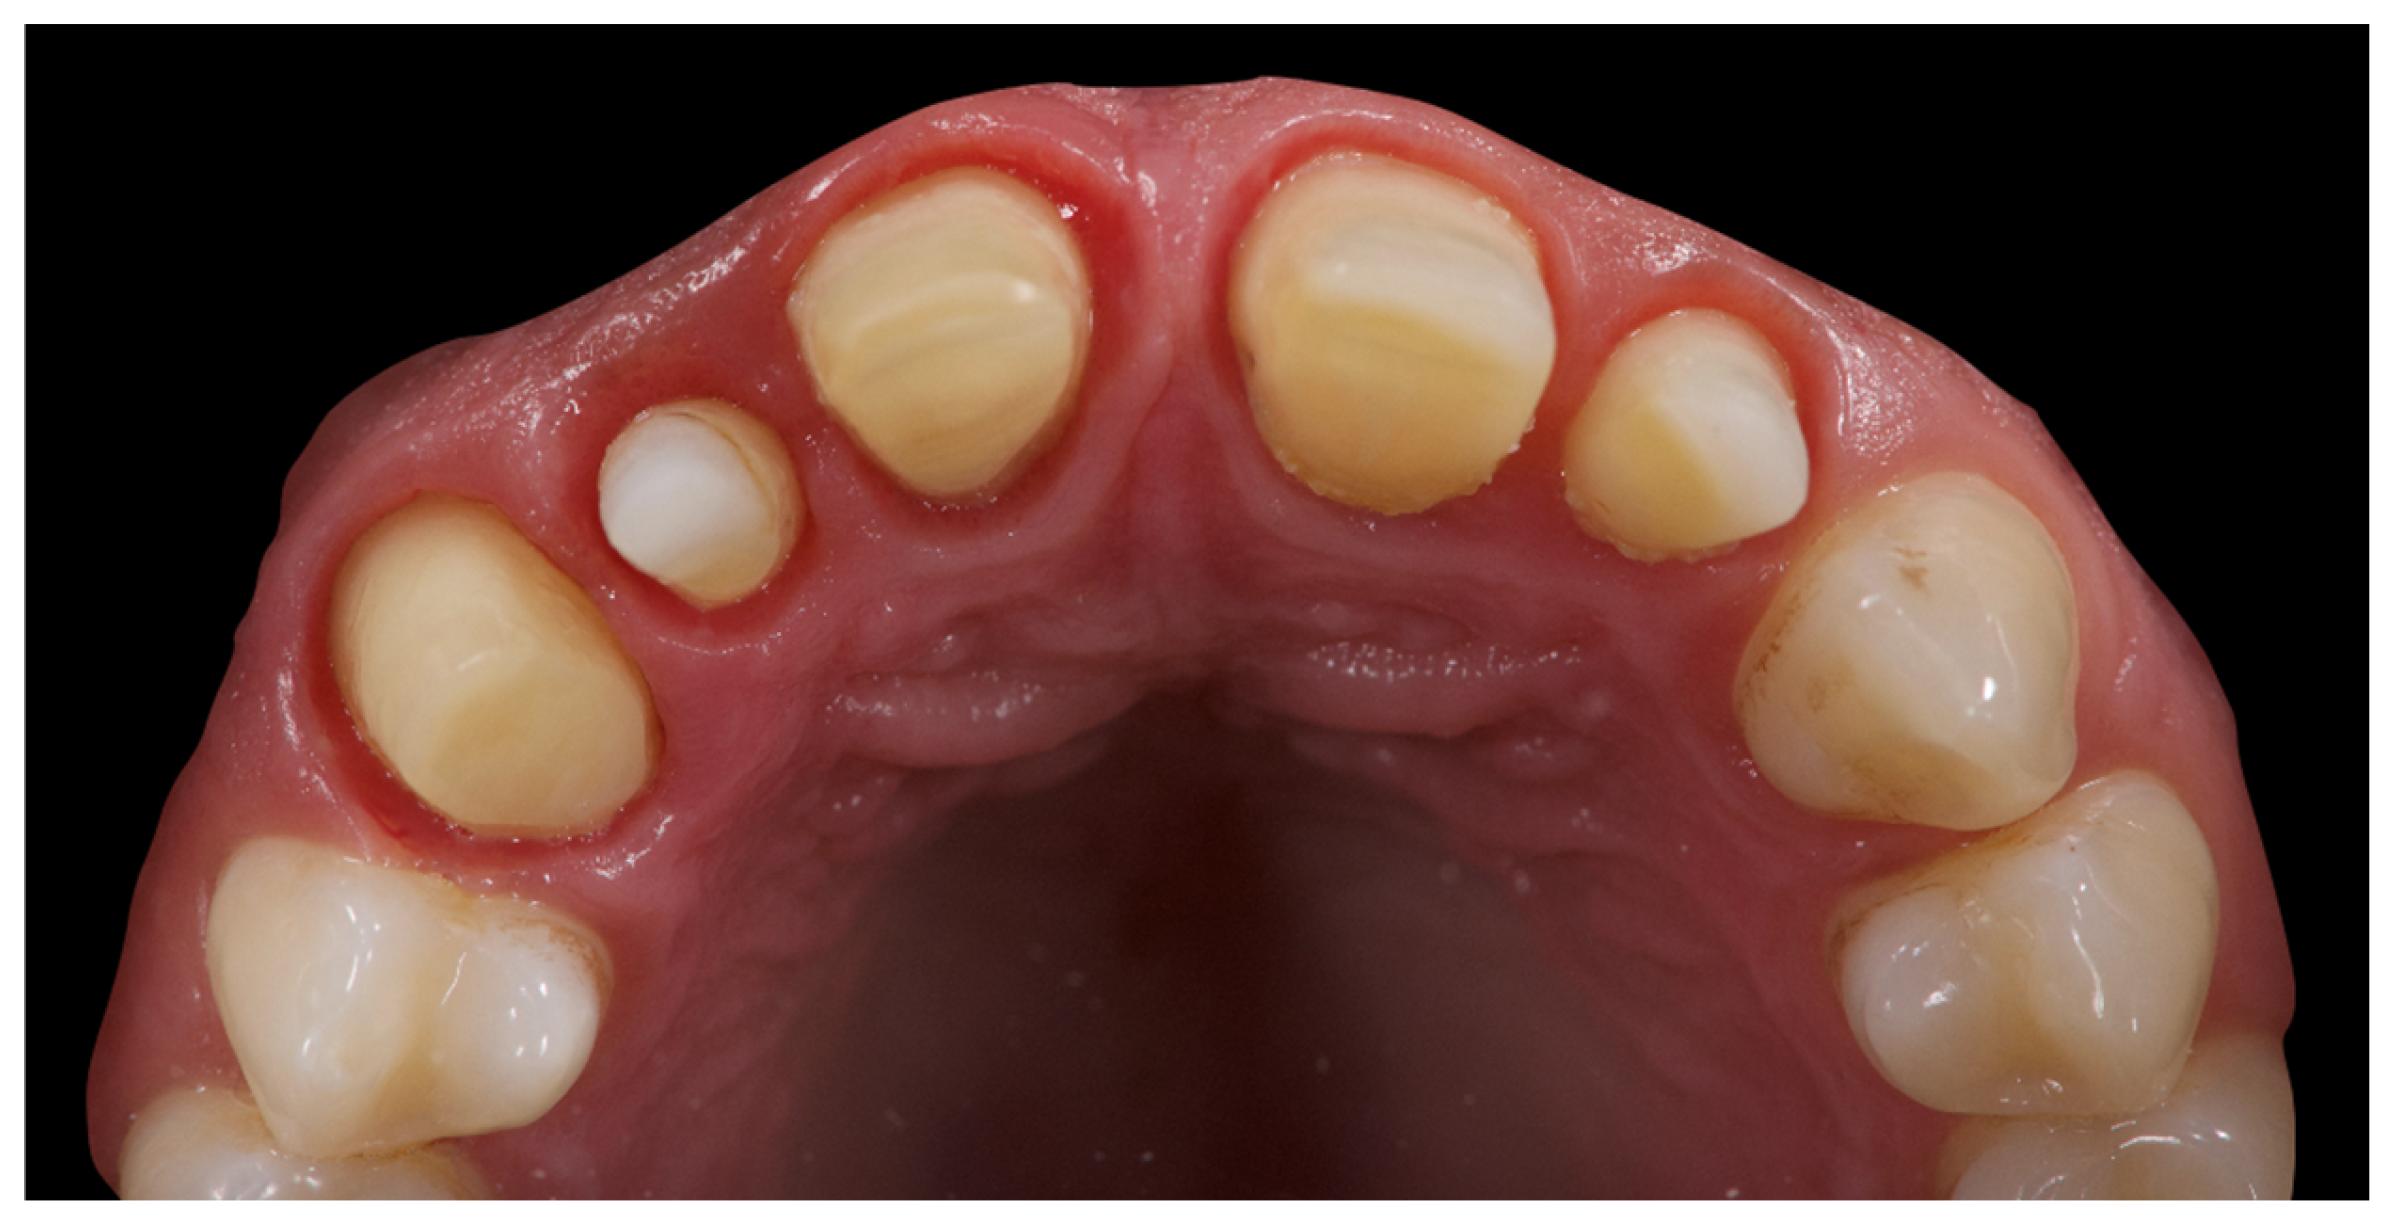

In addition to standard radiographs, a cone beam computed tomography (CBCT) scan was performed to obtain a three-dimensional assessment of the alveolar bone volume and morphology in the anterior maxillary region. Digital intraoral impressions were acquired using the Medit i500 scanner (MEDIT Corp., Seoul, Republic of Korea, Figure 2), complemented by intraoral and extraoral photographic records for comprehensive facial and dento-labial analysis (Figure 3 and Figure 4), as well as an aesthetic predictive simulation using digital smile design software (exocad’s DentalCAD 3.2 Elefsina, Smile Creator, exocad GmbH, Darmstadt, Germany).

Figure 2. Initial intraoral scans.

The initial aesthetic evaluation revealed a 7 mm incisal display at rest, a flat incisal edge morphology, a high smile line, and a smile width encompassing ten teeth with normal buccal corridors. The facial midline was aligned with the interincisal midline, although a diastema was observed between teeth 1.1 and 2.1 (Figure 5).

The occlusal plane appeared canted relative to both the labial commissure and the horizontal reference plane, whereas the interpupillary line was centred. Functional analysis demonstrated a minor discrepancy between the centric relation and maximum intercuspation (0.5 mm), a deep bite, and group function occlusion. An evaluation of maxillary positioning, mandibular dynamics, and temporomandibular joint (TMJ) function was conducted using the Zebris Jaw Movement Analysis System (JMA, zebris Medical GmbH, 88316 Isny, Germany). Periodontal assessment at baseline revealed stage III, grade B periodontitis with a mean probing depth of 2.6 mm, mean sextant probing depth of 4.8 mm, clinical attachment loss averaging 2.2 mm, a plaque index of 12%, bleeding on probing at 16%, and grade I mobility of teeth 1.1, 1.2, 2.1, and 2.2 (Figure 6).